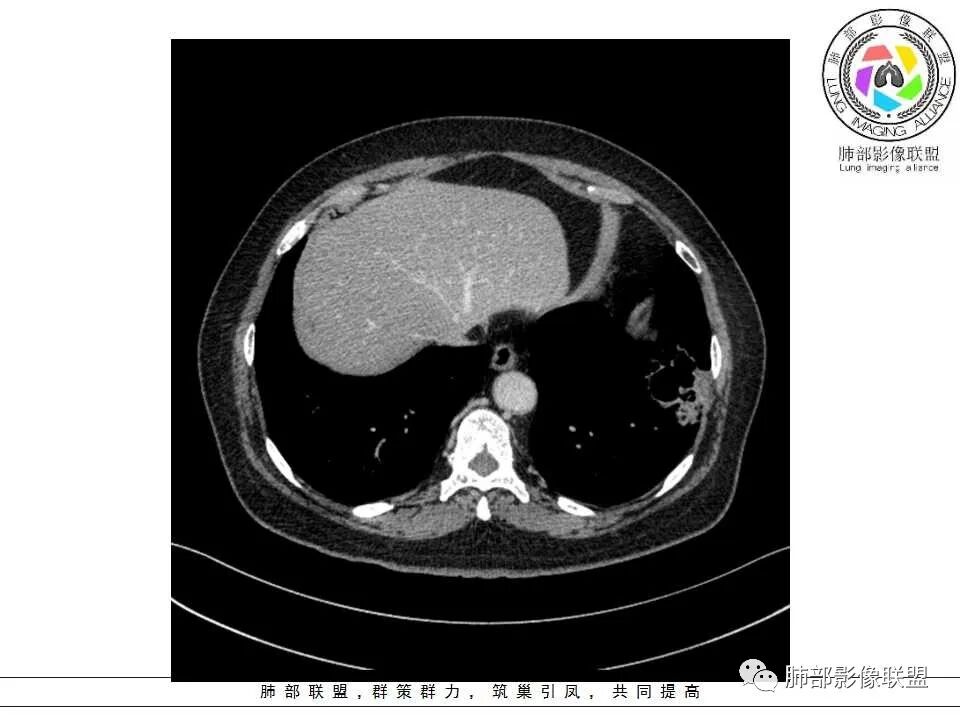

女性,65岁,左肺下叶空腔边缘见不规则结节,结节强化轻、不均匀,局部坏死边界较清楚,胸膜为糊墙为主,膈面胸膜判断不清楚似有结节;空腔内见分隔,或者数个融合,局部张力稍弱,边缘见支气管截断和血管集束;外周见大片磨玻璃影,部分边界模糊。结合病史炎症肯定有,但是囊腔结节这部分感觉恶性征象多过良性,考虑囊腔型腺癌可能性大,鉴别肺大疱感染

左肺下叶外侧基底段空洞,壁增厚,轻度强化,周围磨玻璃影,边界清晰,考虑囊腔型肺癌。

女性,65岁,咳嗽、咳痰2月余,伴发热数日。

胸CT:左肺下叶囊腔,壁厚薄不均,可见壁结节,囊腔内可见断裂小梁,部分融合,周围边界较清楚GGO,胸膜牵拉,可见血管集束、支气管充气征,冠状位部分层面可见支气管在囊腔边缘截断。考虑:囊腔型腺Ca。鉴别:肺大疱感染,CPAM等。

囊腔有张力,外形有分叶,壁厚薄不均,有间隔,有强化

肉眼可见:部分肺组织,大小5*3*3cm,已剖,切面可见2.5*2cm的灰褐色肿物,边界不清,质中等。

病理诊断:(左下肺肿物)浸润性粘液腺癌,累及肺膜,未见明确脉管内癌栓。

免疫组化结果:TTF-1(-),Ki67(阳性细胞约占10%),NapsinA(-),CK7(+),EGFR(+),ALK(-)。

1、左肺下叶外基底段不规则囊腔样病灶,囊腔内有条形影及血管穿行。

2、囊壁薄厚不均匀,稍显僵硬,有壁结节(对应边缘分叶等)、结节强化明显。

以上两条几乎将肺囊肿彻底排除在外,且高度怀疑新生物!

3、灶周环以大范围磨玻璃影,非常均匀,没有重力分布趋势,分叶状,边界隐约可变。

4、冠状位部分层面可见支气管在囊腔边缘截断。

本例囊腔性病灶尽管腔壁稍显僵硬,壁结节凸显,但女性患者,灶周明显磨玻璃晕,都强烈提示为囊腔性腺癌。

病理粘液腺癌确乎意外,非常罕见!

大范围磨玻璃影可以符合粘液腺癌。机制包括分泌黏液的癌细胞沿肺泡壁生长以及含肿瘤细胞的黏液成分沿气道飘散种植等。囊腔形成推测肿瘤等成分形成小支气管的活瓣阻塞所致。